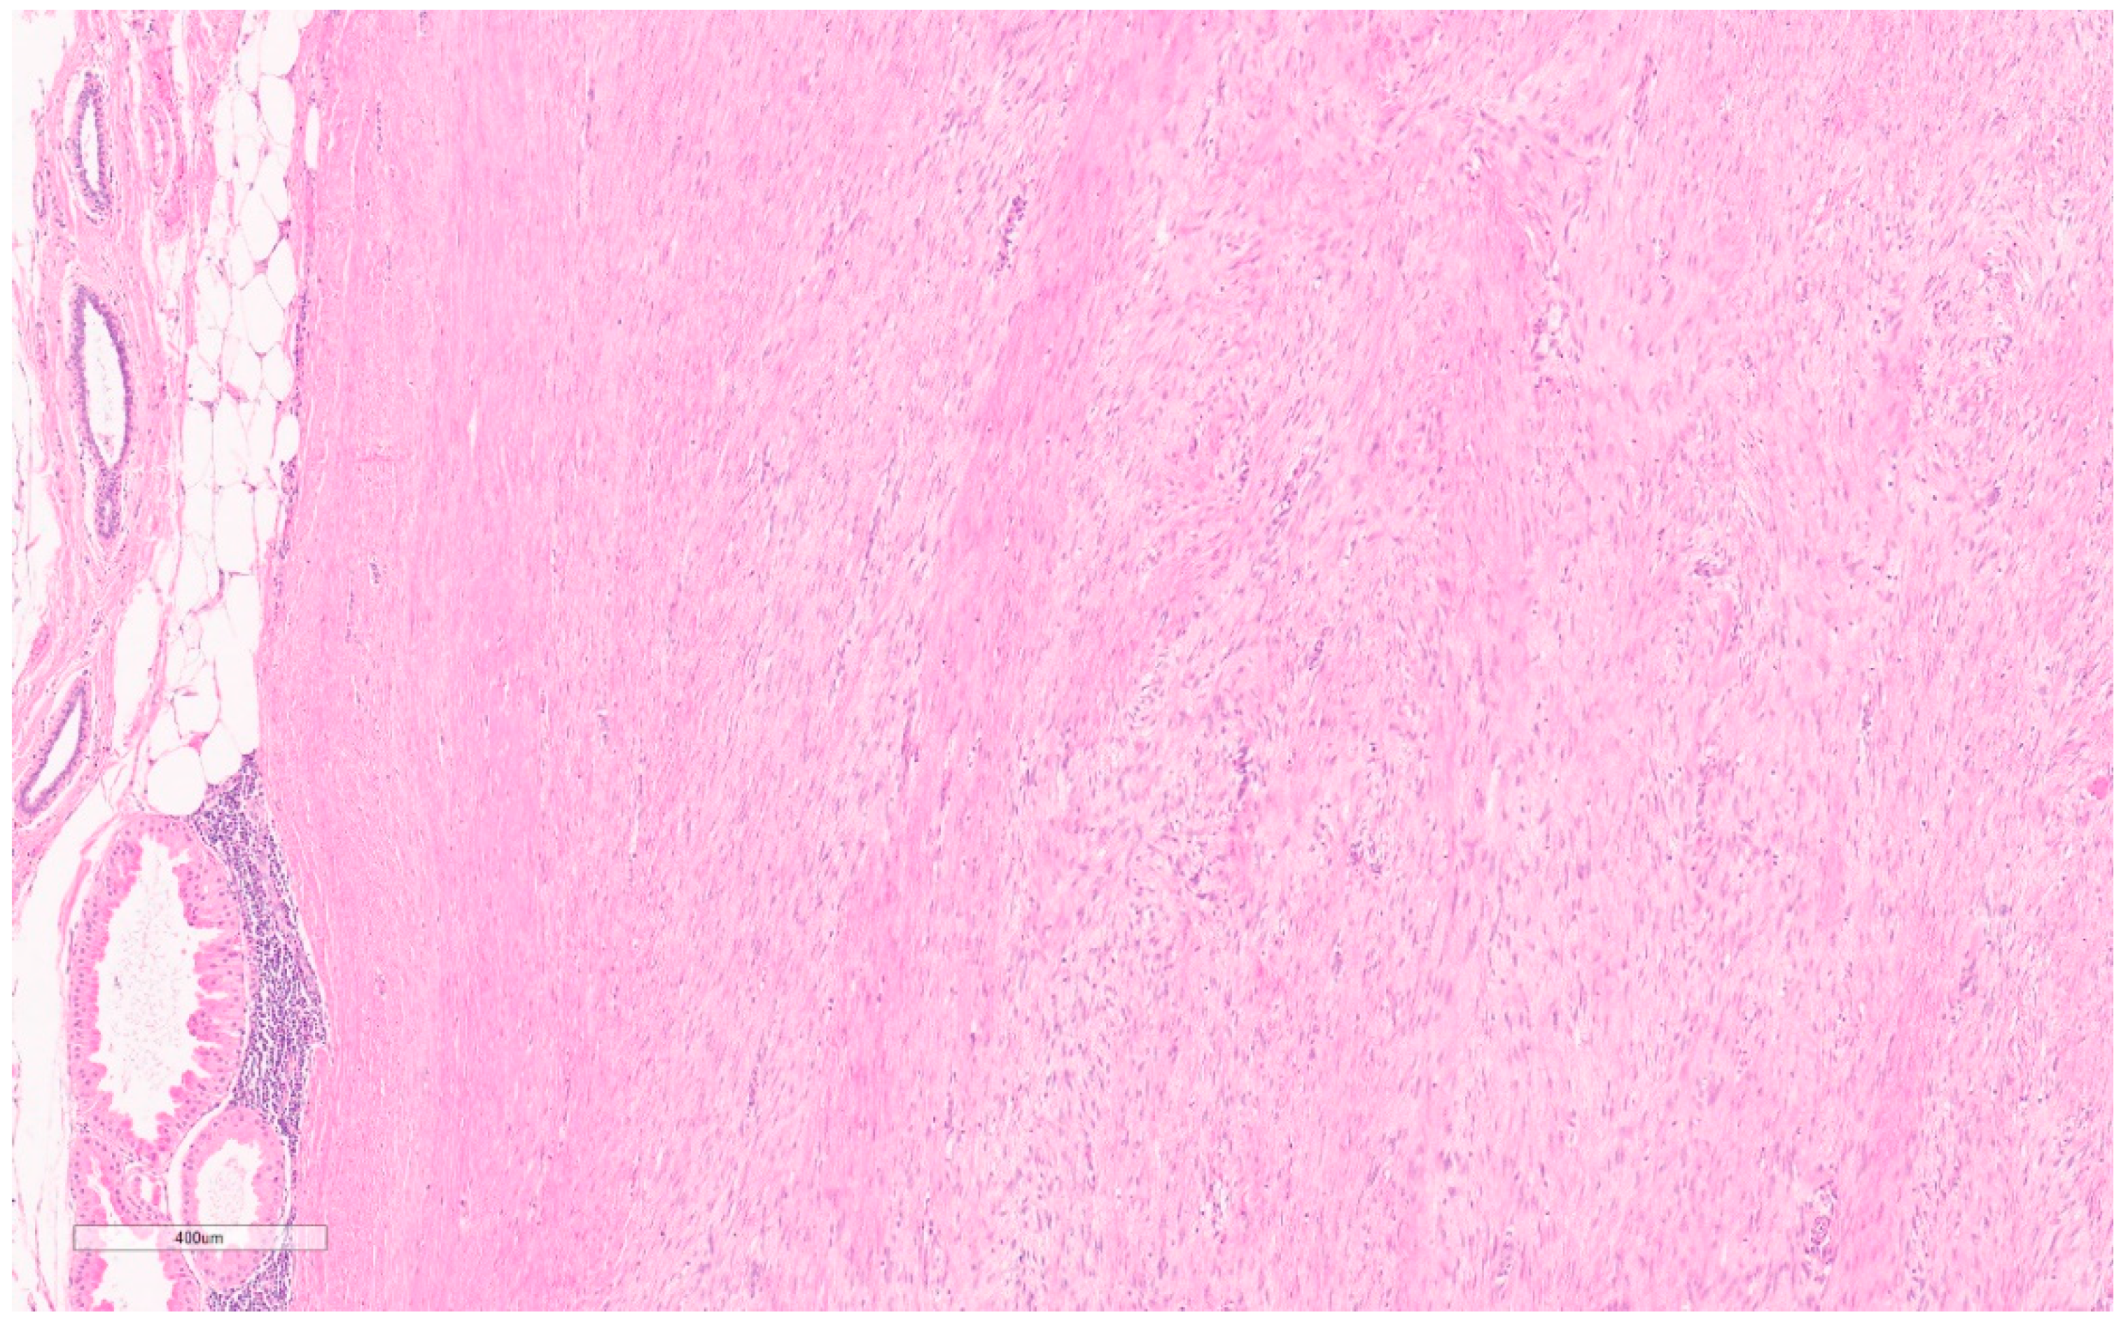

2.3. Fibromatosis/Desmoid Tumor

Summary of Updates